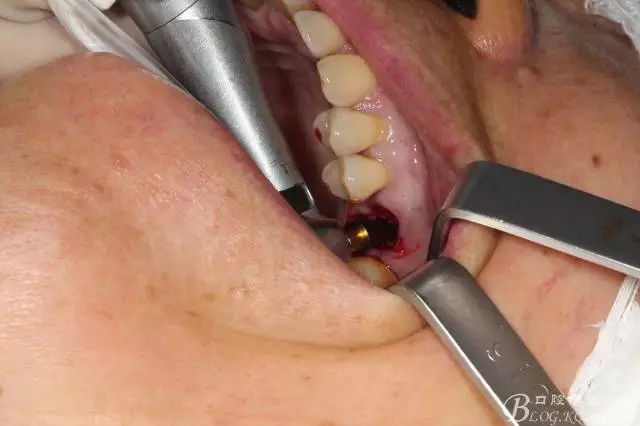

備洞只是稍微修整就可以,因為實在太大了也沒啥好讓我們折騰的骨頭了

備洞的時候當(dāng)然想盡一切辦法讓顎側(cè)骨頭往頰側(cè)推,使得種植體的頰側(cè)有人為做出來的骨壁

植入以后,方向當(dāng)然還是我的強項吧 不過這個種植體稍微靠了點遠(yuǎn)中了